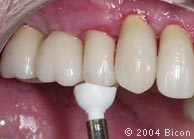

45. | 试戴一体化基台冠。 |